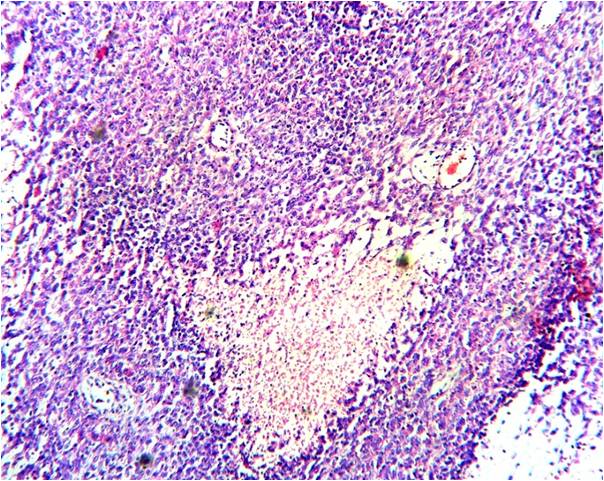

Introduction: Cystic partially differentiated nephroblastoma(CPDN) is a rare tumour of infancy which is considered to be a low risk malignant neoplasm. It has a favourable outcome as compared to classical Wilms tumor.Case history: A 10 month old male child presented with abdominal lump of two months duration. Ultrasound abdomen revealed a cystic mass involving most of the left kidney. After nephrectomy we received a specimen of kidney measuring 7x6x5 cms. Multiple cystic areas were seen along with areas of hemorrhage and a narrow rim of normal kidney.On microscopy, multiple cysts of varying sizes were seen lined by cuboidal, flattened, eosinophilic and hobnail cells. The septa were relatively thick containing bland spindle cells with few foci of blastemal cells .A diagnosis of cystic partially differentiated nephroblastoma was made.Conclusion: CPDN is a rare variant of Wilms tumor with a favorable prognosis. Histopathologic examination helps to differentiate it from other cystic lesions of the kidney and is of therapeutic importance.References